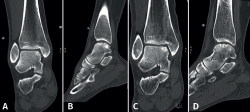

Las técnicas de fijación han demostrado éxito clínico y radiológico en 8 de cada 10 pacientes y el éxito también se ha mantenido a largo plazo (Figuras 5 y 6). Dado que estas técnicas preservan el cartílago hialino y proporcionan una cicatrización superior del hueso subcondral, resultan ventajosas frente a otras opciones de tratamiento quirúrgico de las OLT, cuando son factibles(39,41).

Figura 5. Tomografía computarizada preoperatoria (A y B) y postoperatoria al año (C y D) de un paciente tras la fijación.